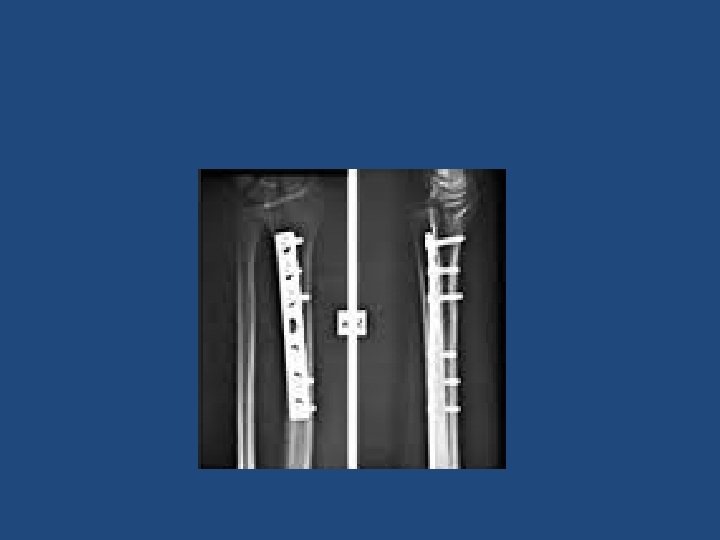

Treatment • Both bone fracture: – Reduce and splint at ER/clinic (temporary) – Are treated almost always with ORIF: (plate and screws) • Monteggia fracture: – ORIF ulna and close reduction of radial head • Galeazzi fracture: – ORIF radius and close reduction of DRUJ.

• Extra-articular fractures: – Close reduction and cast application. – Immobilization for 6 -8 weeks. – ROM exercises after cast removal. – Surgery: if reduction is not accepted • Intra-articular fracture: – a step more than 2 mm is an indication for surgery. – ORIF with plate and screws.

Treatment • If fracture is intracapsular: – Displaced: hemiarthroplasty – Not displaced: close reduction and Screw fixation. • If fracture is Extracapsular: – Close reduction and DHS or IM nail fixation